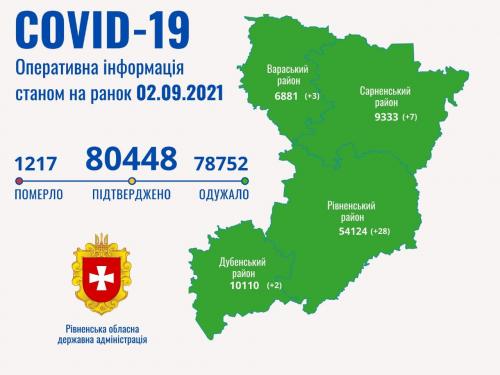

Коронавірус повертається: як стрімко зростає кількість хворих на Рівненщині (ВІДЕО)